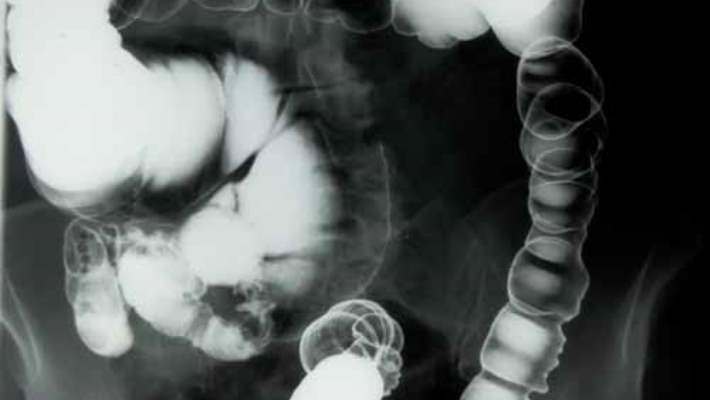

Kolon kanserini tespit etmenin tek yolu kolonoskopidir.

Kolonoskopi en iyi tarama testi olsa da, esnek sigmoydoskopi (video görüntüleme), baryum fitili ve dışkı testi gibi başka testler de mevcuttur.

Araştırmacılara Göre Yüksek Tanımlı Kolonoskopi Daha Fazla Polip Tespit Ediyor